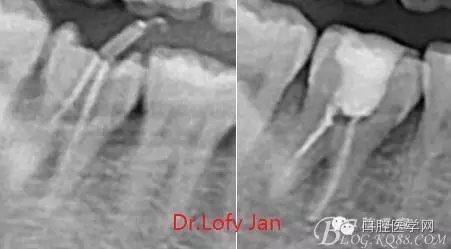

前言:自己做的一些曲面斷層片在未試尖根管治療中的病例整理,發(fā)現(xiàn)問題很多包括自身的,技術(shù)的,還有設(shè)備的問題,予以總結(jié)整理并期待進(jìn)一步提高。

根管治療術(shù)是牙體牙髓疾病治療中最復(fù)雜和最關(guān)鍵的治療項(xiàng)目。根管充填材料抵達(dá)根尖、并能嚴(yán)密堵塞根尖孔,是確保根管治療效果的關(guān)鍵指標(biāo)。為了保證根管充填到位,醫(yī)生需要在術(shù)前照牙片以了解牙根根管的數(shù)量、彎曲程度和長度,在術(shù)中有時(shí)需要插針照牙片來精確測量根管長度,術(shù)后必須照牙片以確定是否根管充填到位,如果欠填或超填,就需要重新充填、重新照牙片確認(rèn),直到根管充填到位。所以,在患者接受根管治療時(shí)有時(shí)會反復(fù)照牙片。

病例分析:曲面斷層片在x線輔助診斷與檢查中目前大多數(shù)文獻(xiàn)和著作都建議只能作為初診拍片檢查手段,不能作為終末疾病的確診與手術(shù)療效的評價(jià)指標(biāo),臨床大部分中小型門診都因?yàn)樵O(shè)備不齊全導(dǎo)致信息偏差很大。